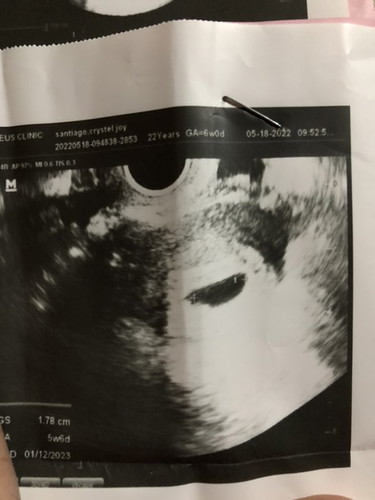

BLIGHTED OVUM ‼️

Hi mga mommy’s 😊 Share ko lang expirience ko about blighted ovum ;) I’am blighted ovum sa first ultrasound ko 5 weeks & 6 days ako non . At wala talaga literal na nakita 💔 Ang sakit para sa akin kasi nakunan na ako sa first baby ko at ang kso nun is NO HEART BEAT 💔 So balik tayo , after nun sabi sa akin ng ob ko is ang blighted ovum is bugok na itlog sya :( Kaya niresetahan ako ng folic acid , vitamins at bonina milk . Pagtapos after 2weeks balik ako para magpaultrasound ulit to make sure na kung may mabubuo o hindi talaga sya totally nadevelop . After nun sinunod ko lahat ang bilis bawala maalat at more water inom gamot gatas . 2 weeks nakabalik na ako sa ultrasound syempre hindi na ako naghahangad na mabubuo si baby ksi sa napapanuod ko sa youtube at kung saan pa is hindi talaga nabubuo ang baby 💔 So ayun turn ko na para sa ultrasound wala akong kaba na nararamdaman kundi lungkot nalang habang nakahiga ako ksi handa na ako sa result tahimik lang ako , pagtapos nun nagulat nalang ako kasi sabi saakin ni doc “ AYUN BABY MO OH “ 😳 So na shock ako ng bongga as in napaupo ako sa gulat at tinignan ko 😭 Meron nga sya at may HEART BEAT NA DIN SYA 😭😭😭❤️ Sobrang tuwa ako napa THANK YOU LORD ako at THANK YOU DOC 😂 Sobrang nakakatuwa ksi nakikita ko tibok ng baby ko , pagtapos sinabi ko agad sa housemate ko (asawa ko) HAHAHA sobrang tuwang tuwa din hahaha So ayun sa mga MOMMY’s dyan pinagaan loob ko THANK YOU SAINYO ika nga DON’T LOSE HOPE ❤️ Kung natatandaan nyo pa ako hahaha sana mabasa nyo ito mahal ko na kayo 💕 Lagi lang magdasal at wag laging negative wag magpakastress focus ka lang kay baby at magiging ok din ang lahat 😊 And now i’m 8 weeks 3 days preg at sana magtuloy-tuloy si baby at hindi na kunin sa akin ❤️ ayun lang SALAMAT SA INYO ‼️‼️ UNAG PICTURE IS WALA PANG BABY AT YUNG PANGALAWA AYUN NAGPAKITA NA SYA . #1stimemom #firstmom #pregnancy #pregnancy